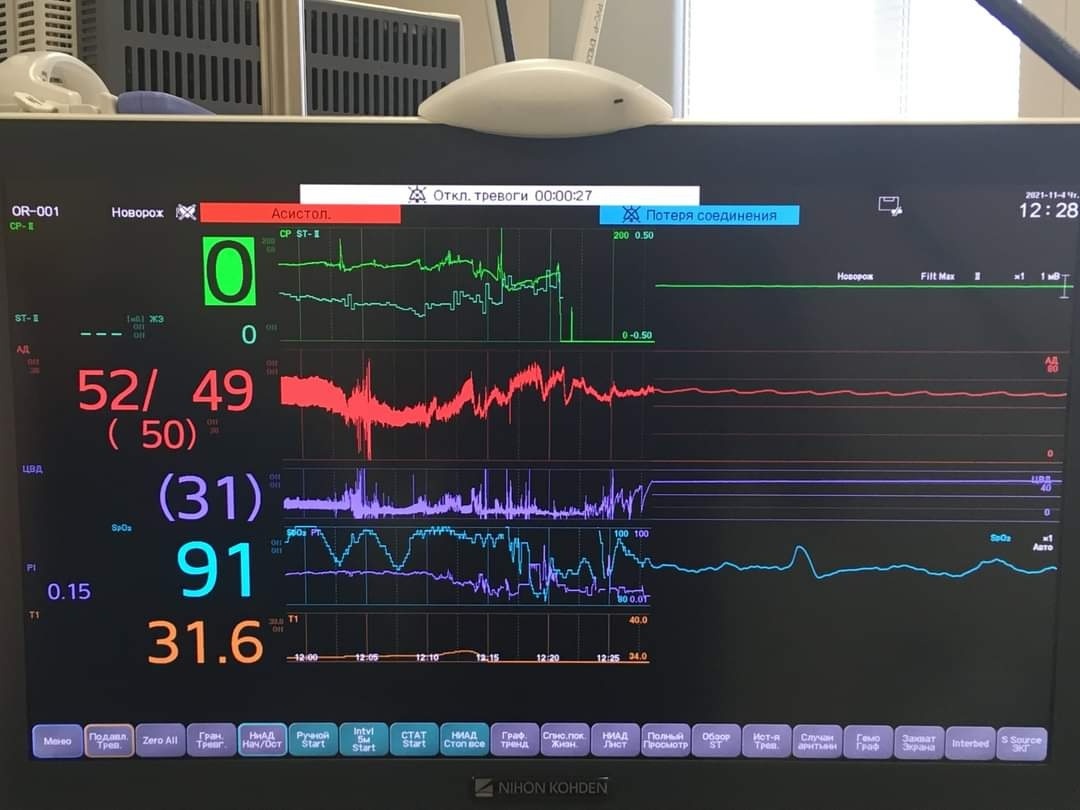

У Дніпрі лікарі міської багатопрофільної клінічної лікарні матері та дитини ім. проф. М. Ф. Руднєва провели унікальну операцію на відкритому серці двомісячному немовляті зі складною патологією – вадою серця та вродженим стенозом трахеї. Для радикального втручання серце зупиняли на 38 хвилин. Дитина дихала за допомогою штучного кровообігу.

«Для стабілізації стану дитини провели перший етап лікування – закриття артеріального протоку. Використовуючи досвід наших європейських партнерів, провели балонну дилатацію трахеї для радикальної корекції вади серця в умовах штучного кровообігу. Це робили на зупиненому на 38 хвилин серці. Вдячні нашим колегам, команді кардіохірургів з Інституту серця МОЗ України, які теж брали участь в операції. Наразі стан дитини – стабільний. Дівчинка переведена з реанімації до відділення патології новонароджених. Досвід саме такої операції мали вперше», – розповів під час пресконференції заступник медичного директора міської багатопрофільної клінічної лікарні матері та дитини ім. проф. М. Ф. Руднєва Олександр Романенко.

За словами завідувача кардіохірургічного відділення згаданої лікарні Павла Павлова, завдяки проведеній операції дитина може самостійно дихати і має усі шанси на подальше здорове життя.

«На апараті штучної вентиляції дитина перебувала упродовж трьох тижнів. Під час операції усунули усі внутрішньосерцеві вади. А завдяки процедурі балонній дилатації усунули патологію трахеї. Коли три дні тому прибирали трубочку у дитини, був такий бентежливий момент, бо не знали чи зможе вона повноцінно самостійно дихати. Те, що ми зараз спостерігаємо, – наші зусилля увінчалися успіхом. Це дуже радує. Дитина самостійно дихає без усіляких підтримок. Звісно, провести таку операцію вдалось завдяки сучасному обладнанню, яке маємо у лікарні», – додав Павло Павлов.